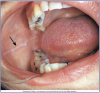

Figure 6 – Buccal Mucosa (Courtesy of Modern Dental Assisting, 10th Edition, Bird et al, Figure 10.5). Photograph of mucosa in the back of the mouth.

Figure 6